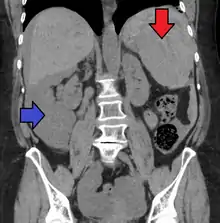

| Spleen ruptured by trauma | |

Splenic rupture is usually evaluated by FAST ultrasound of the abdomen.[3] Generally this is not specific to splenic injury; however, it is useful to determine the presence of free floating blood in the peritoneum.[3] A diagnostic peritoneal lavage, while not ideal, may be used to evaluate the presence of internal bleeding a person who is hemodynamically unstable.[4] The FAST exam typically serves to evaluate the need to perform a CT.[4] Computed tomography with IV contrast is the preferred imaging study as it can provide high quality images of the full peritoneal cavity.[3]